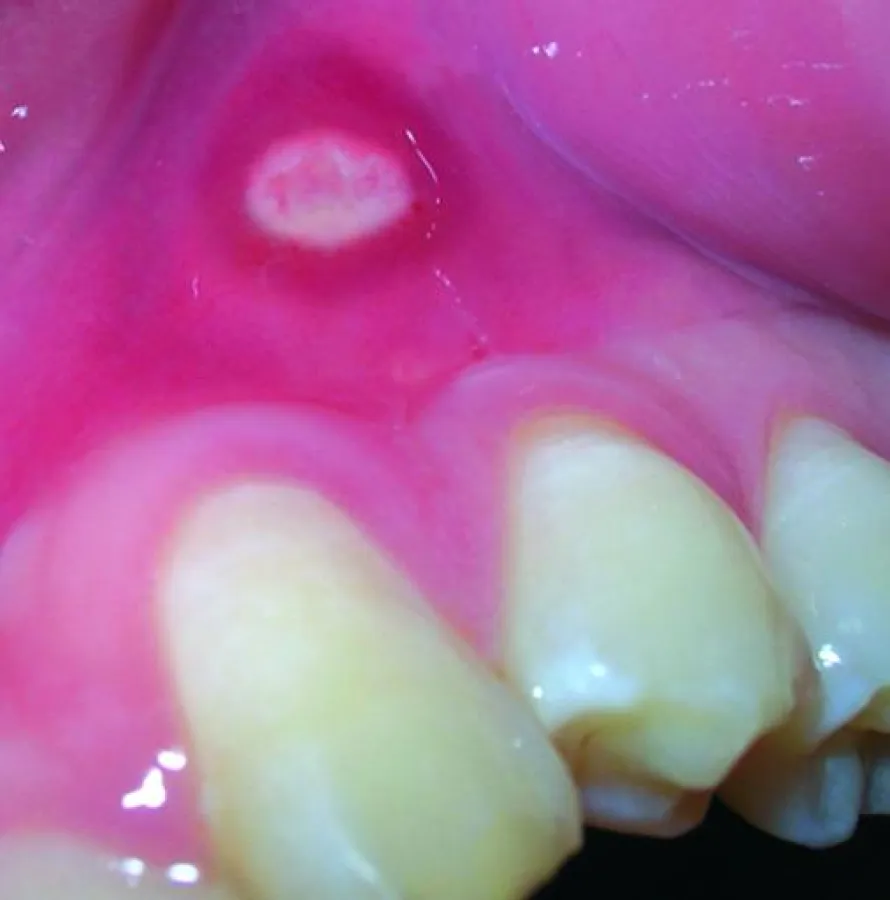

(openPR) Endlich gibt es auch in Deutschland ein effektives Mittel zur akuten und prophylaktischen Behandlung von chronisch rezividierenden Aphthen und Stomatitis aphthosa. Jeder vierte Deutsche macht zumindest einmal in seinem Leben die schmerzhafte Bekanntschaft mit Aphthen, diesen kleinen weißen Flecken im Mundraum, die die Nahrungsaufnahme -manchmal sogar das Sprechen- zu einer unangenehmen Sache werden lassen. Meist verschwinden die kleinen Plagegeister nach etwa 10 Tagen so unerklärlich, wie sie gekommen sind. In jedem 10ten Fall aber werden Aphthen zu einem chronischen Leiden. Hinter diesen rein statistischen Daten verbergen sich jährlich etwa 250.000 neu betroffene Patienten, die unter chronisch rezividierenden Aphthen leiden und denen bisher meist nur durch den Einsatz cortisonhaltiger Präparate Linderung verschafft werden konnte. Nun kommt aus Schweden ein neues und rein pflanzliches Mittel: Sinaftin®. Das Therapeutikum Sinaftin® ist das Resultat achtjähriger intensiver Forschungsarbeit. Fünf Jahre klinische Untersuchungen an der Universitätszahnklinik in Göteborg unter Leitung von Prof. Dr. Mats Jontell haben ein wirksames Mittel gegen chronisch rezividierende Aphthen und Stomatitis aphthosa hervorgebracht. Sinaftin® wurde bereits 2004 auf der Swedental, Skandinaviens größter Dentalmesse, vorgestellt. Das Therapeutikum wird heute von der schwedischen Zahnärzteschaft und den Betroffenen empfohlen und entwickelt sich in Schweden zur Standardtherapie bei rezividierenden Aphthen. Nun steht Sinaftin® endlich auch Betroffenen in Deutschland zur Verfügung. Die patentierte Zusammensetzung, die ohne chemische Zusätze auskommt, bietet eine echte Alternative zur Behandlung mit Cortison oder chirurgischem Eingriff. Eine umfassende Doppelblindstudie mit Placebokontrolle zeigte, dass 51% der Patienten nach Behandlung mit Sinaftin® vollkommen beschwerdefrei waren, bei weiteren 20% wurde eine wesentliche Verbesserung festgestellt. Anteil an diesem Erfolg hat sicher auch die einfache Applikation von Sinaftin: sie wird vom Betroffenen einfach an Stelle der Zahnpasta verwendet. Wie bekannt, haben sich auch andere Zahnpasten bei manchen Patienten als bedingt wirksam gegen Aphthen erwiesen, die genauen Ursachen blieben jedoch weitgehend unbekannt. Ein wichtiges Ziel der Forschung war es daher, die Wirkstoffe und Wechselwirkungen bestimmen zu können, die den Heilungsprozess von Aphthen beschleunigen und deren Neuentstehung verhindern. Im Gegensatz zu herkömmlichen Zahnpasten enthält Sinaftin® auch kein Natriumlaurylsulfat, da die klinischen Untersuchungen hier eine eindeutig negative Beeinflussung des Heilungsprozesses erwiesen haben. Sinaftin® verhindert die Bildung von Plaque und soll, wie jede Zahnpasta, mindestens zweimal täglich, morgens und abends, verwendet werden. Bei regelmäßiger Anwendung verschwinden bereits vorhandene Aphthen und deren erneutes Entstehen wird verhindert. Zur Behandlung akuter Aphthen sollte Sinaftin® mit einem Wattestäbchen mehrmals täglich auf die Aphthe aufgetragen werden. Sinaftin® ist darüber hinaus auch hervorragend geeignet für Patienten mit empfindlichen Zahnhälsen. Dank der einzigartigen Zusammensetzung werden die Dentinkanäle für äußere Reize blockiert und das Schmerzempfinden verschwindet. Die Forschungsergebnisse der Studie „The Effect of a Dentifrice in the Prevention of Recurrent Aphthous Stomatitis“ können interessierte Ärzte und Heilpraktiker auf der Internetseite des Anbieters herunterladen (www.sinaftin.de). Dort finden Sie auch weitere Informationen.